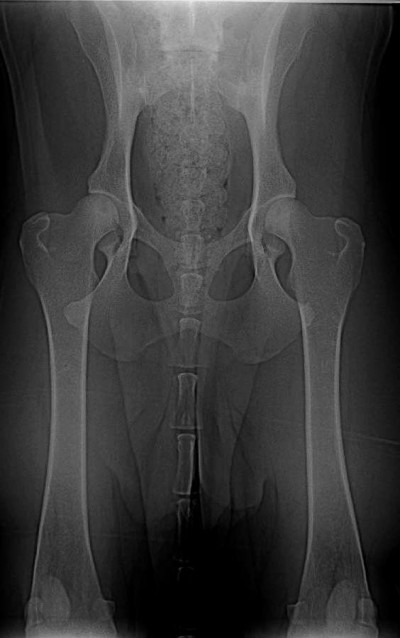

Grifovi je dnes skoro sedm let, a navzdory předpovědím chodí. A velkou zásluhu na tom má plavání. Podívejte se na rentgeny a přečtěte si jak se nám to podařilo. Tímto článkem bych také chtěl dát trochu naděje těm, kteří mají štěně či psa, který přestal chodit a má dysplazii kyčlí.

Znovu na rentgenu jsme byli ve zhruba čtyřech letech, kdy Grif prodělal amputaci plovací blány, protože se mu po zánětu udělala boule velikosti velkého vlašského ořechu. Rentgen, který zde vidíte je poslední, ze skoro sedmi let, kdy jsme byli na operaci s předním loktem, artrózu bylo nutné odfrézovat. Ano, to byla poslední zatím neoperovaná noha. Pro přehled je vedle další rentgen zdravého psa (mladého leonbergera). Prohlédněte si oba klouby.